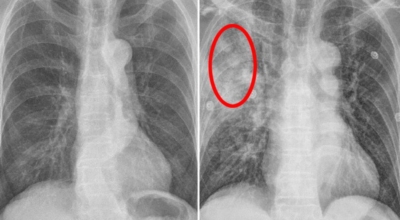

폐렴 증상이 있는 경우 X선 촬영 및 배양 검사로 진단할 수 있답니다. 필요에 따라 소변, 혈액, 혈청 검사, CT 등을 추가로 실시합니다. 폐렴 진단을 받은 환자는 일반적으로 입원을 권장하지 않지만 젊거나 기초질환이나 호흡곤란이 심한 경우, 고령, 임신 등의 경우 병원에 내원하여 상황에 맞는 신속한 치료와 상태 개선, 위험관리를 받는 게 좋아요.